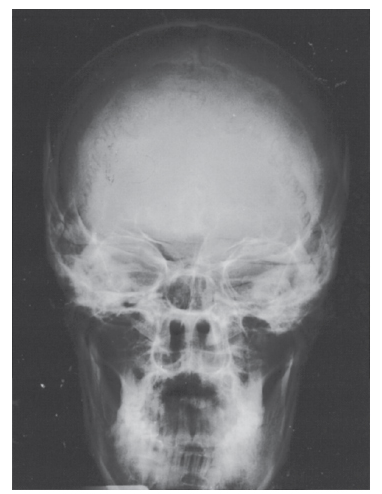

A parietoacanthial projection (Waters position) of the skull is shown. The chin is elevated sufficiently to project the petrous ridges below the maxillary sinuses (number 4). Note that the foramen rotundum is seen near the upper margin of the maxillary sinuses. Other paranasal sinus groups are not well visualized in this position, although a modification with the mouth open may be taken to demonstrate the sphenoidal sinuses. This is also the single best projection to demonstrate the facial bones. The zygomatic arch (number 2) is well demonstrated; the mandible, its angle (number 1), and the coronoid process (number 3) are also well demonstrated. The odontoid process is seen projected through the foramen magnum. The mastoid air cells are seen adjacent to the mandibular angle as multiple small, air-filled, bony spaces.

C - Zygomatic arch The parietoacanthial projection (Waters method) demonstrates a distorted view of the frontal and ethmoidal sinuses. The maxillary sinuses (number 4) are well demonstrated, projected free of the petrous pyramids. This is also the best single position for the demonstration of facial bones. The mandibular angle is illustrated by number 1, the zygomatic arch by number 2, and the coronoid process by number 3.